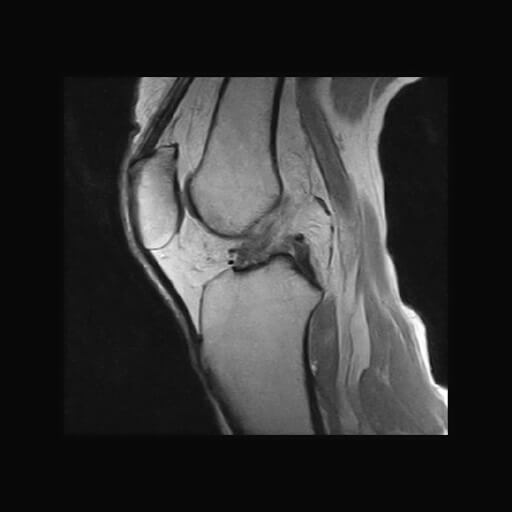

MRI検査